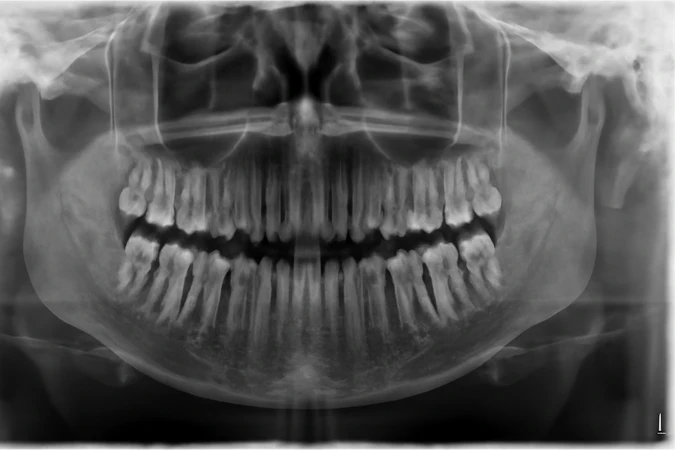

Pemeriksaan rontgen gigi lengkap yang menampilkan gambaran rahang secara menyeluruh sekaligus analisis posisi gigi dan tulang wajah.

Panoramic adalah jenis rontgen gigi yang dapat menangkap seluruh mulut dalam satu gambar tunggal. Termasuk gigi, rahang atas dan bawah, struktur dan jaringan di sekitarnya.

Rontgen gigi ini menggunakan sensor digital, maka hasil foto rontgen yang dihasilkan tampak lebih jelas.

Fungsi rontgen panoramic

- Melihat keadaan seluruh mulut, termasuk tulang dan gigi, dalam bentuk datar

- Menemukan gangguan dalam mulut, seperti gigi bertumpuk, tulang rahang yang abnormal, kista, tumor, infeksi, atau patah tulang

- Merencanakan terapi untuk memperbaiki susunan gigi yang tidak rapi, seperti gigi palsu, kawat gigi, cabut gigi, dan implan gigi

Bagaimana pemeriksaan dengan rontgen panoramic dilakukan?

- Pasien diminta menggigit sesuatu, lalu mesin rontgen berkamera akan memutari seluruh sisi kepala